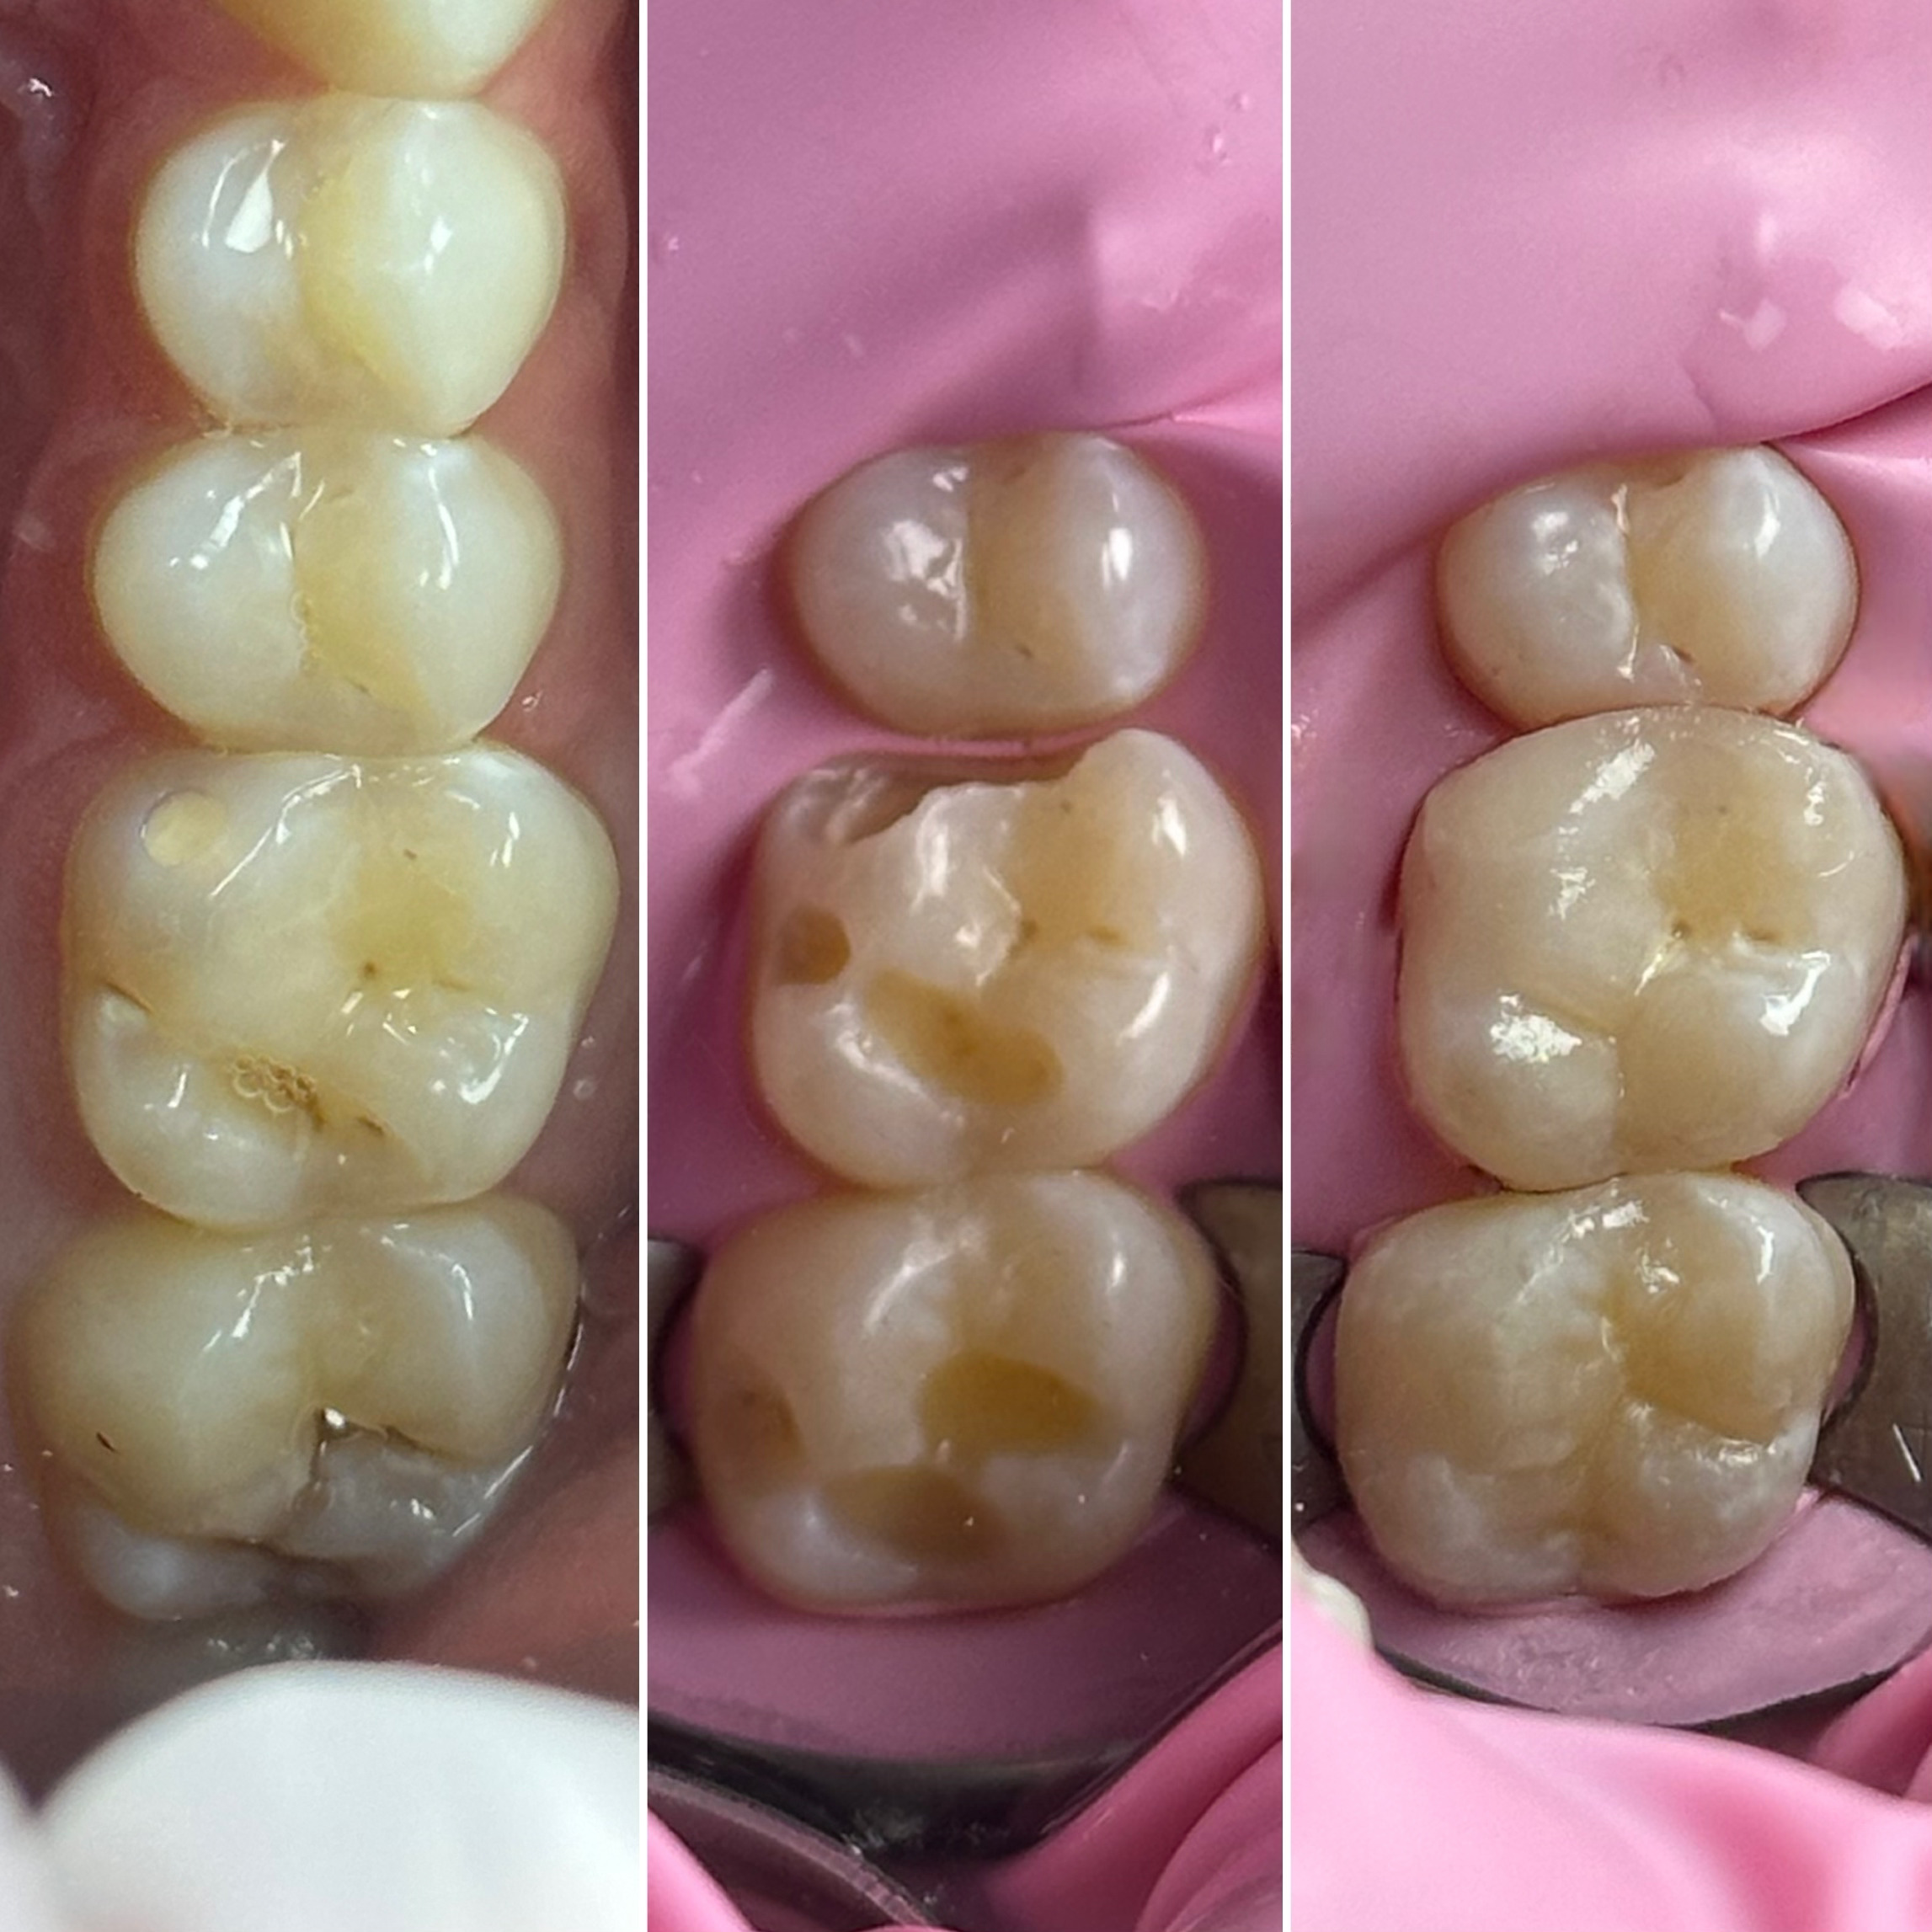

• Диагностика и лечение кариеса и его осложнений (пульпиты, периодонтиты)

• Художественная реставрация фронтального и бокового участка зубов

2022 год – «Прямая реставрация.Боковой сегмент.» Игорь Гудыма